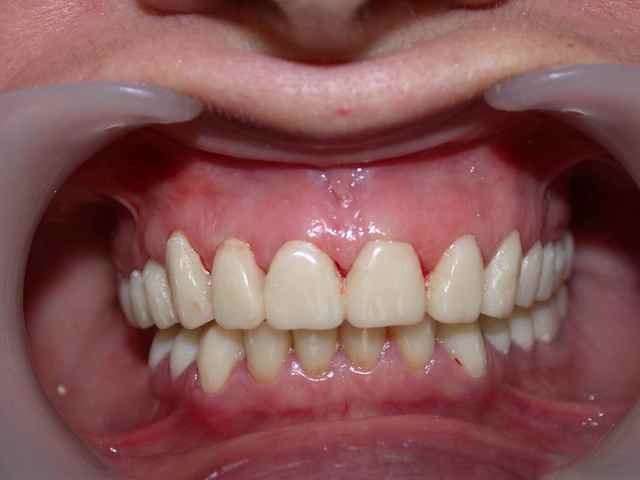

pour poursuivre la fin du cas la pose en mai 2006

du travail conventionnel (que j'espère définitif...)

plusieurs remarques :

je me suis un peu battu avec cette patiente pour la maintenance (bloc incisif inférieur..)

teinte A1 souhaitée par la patiente.

j'ai d'ailleurs réalisé un blanchiment en 2007 des 4 incisives inférieures pour aligner la teinte (en fait une fois que la maintenance a été meilleure ).

photo prise en juillet 2007